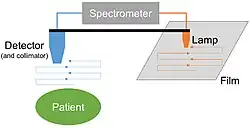

Cassen's original rectilinear scanner used calcium tungstate (CaWo4) crystal as the radiation detector. Later systems used a Sodium iodide (NaI) scintillator, as in a gamma camera.[7] The detector must be connected by mechanical or electronic means to an output system. This could be a simple light source over photographic film, dot matrix printer, oscilloscope or television screen.[8][9][10]

The patient is administered with a radioactive pharmaceutical agent, such as radio-iodine which will naturally collect in the thyroid. The detector moves in a raster pattern over studied area of the patient, making a constant count rate. A collimator restricts detection to a small area directly below its position so that by the end of the scan emission from the whole study area has been detected. The output method is designed such that positional and detection information is maintained. For example, when using a light source and film the light is moved in tandem with the detector, and the intensity of light produced increases with an increase in activity, producing dark areas on the film.[11][12]